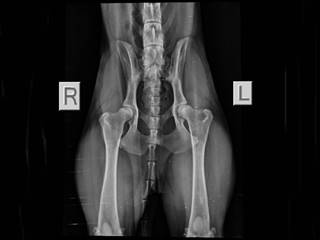

Behinderungen/Krankheiten: Subluxation des Hüftgelenks

Aufgefallen ist hinten eine leichte, temporäre Lahmheit. Wir haben ihn zum Röntgen bringen lassen, und man erkennt eine Subluxation links, sprich er hat eine "lockere Hüfte". Wie wir Frederik nun helfen können, dass er auch weiterhin lebensfroh und schmerzfrei durch´s Leben laufen kann, möchten wir gerne von einem Fachtierarzt abklären lassen, was aber im Moment nur hierzulande möglich ist.

Daher suchen wir dringend einen Platz für den lieben Kerl, wo auch eine Nachsorge, falls operiert werden muss, gewährleistet ist. Die anfallenden Kosten übernehmen selbstverständlich wir!

Auf dem Weg zu einem erneuten Röntgen...

...alles schaut gut aus :-)!